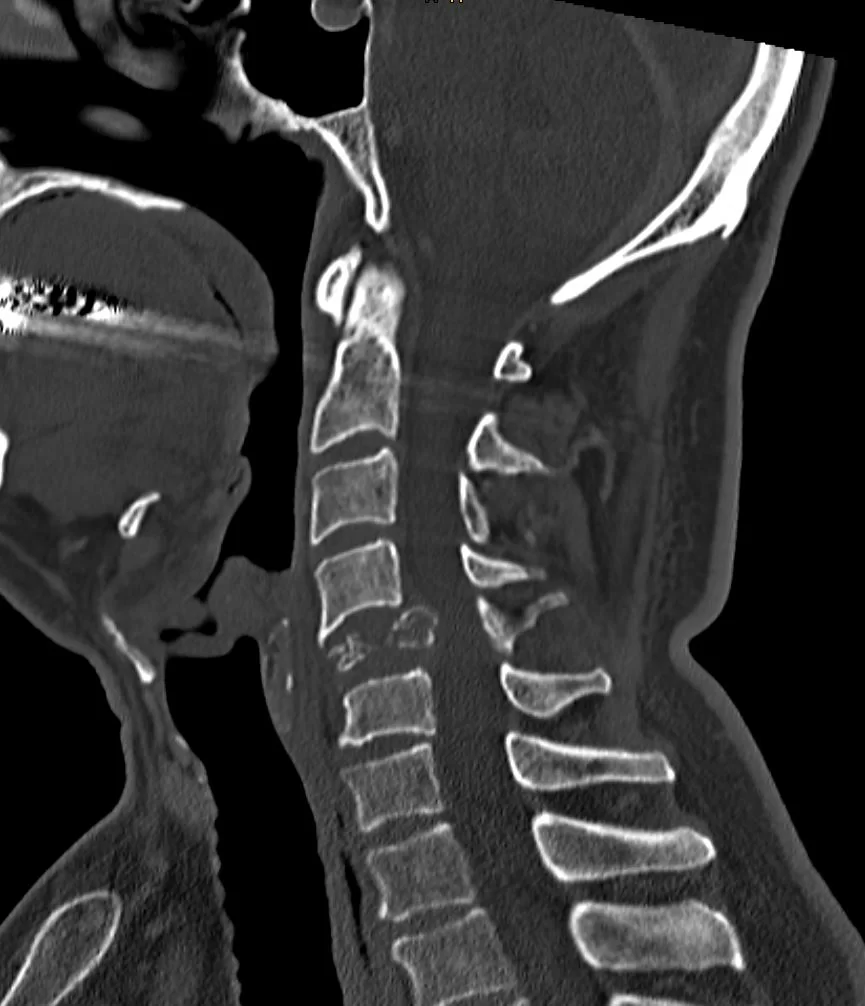

Ασθενής άδρας 60 ετών με εμμένουσα αυχεναλγία (3 εβδομάδες) και πάρεση του δεξιού άνω άκρου απο πενθημέρου.

Ο απεικονιστικός έλεγχος έλεγχος με μαγνητική και αξονική τομογραφία της αυχενικής μοίρας της σπονδυλικής στήλης ανέδειξε παθολογικό κάταγμα του Α5 σπονδύλου στα πλαίσια νεοπλασίας.

Διενεργήθη σωματεκτομή του Α5 σπονδύλου και σπονδυλοδεσία/στήριξη της σπονδυλικής στήλης με διατεινόμενο κλωβό και πλάκα.